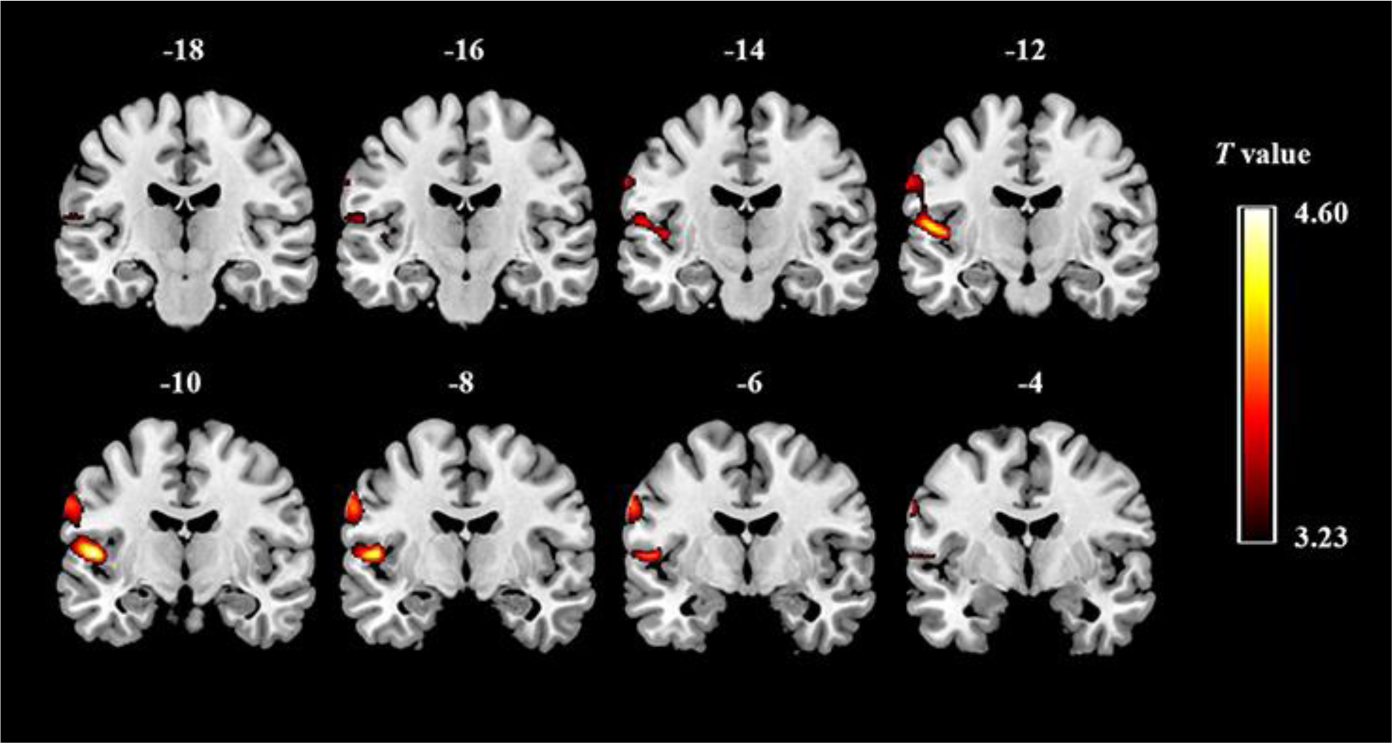

| [50] | Chen RJ, Sharma S (2025) GABA Receptor. StatPearls . Treasure Island (FL): StatPearls Publishing. |

He JL, Oeltzschner G, Mikkelsen M, et al. (2021) Region-specific elevations of glutamate + glutamine correlate with the sensory symptoms of autism spectrum disorders. Transl Psychiatry 11: 411. https://doi.org/10.1038/s41398-021-01525-1

|